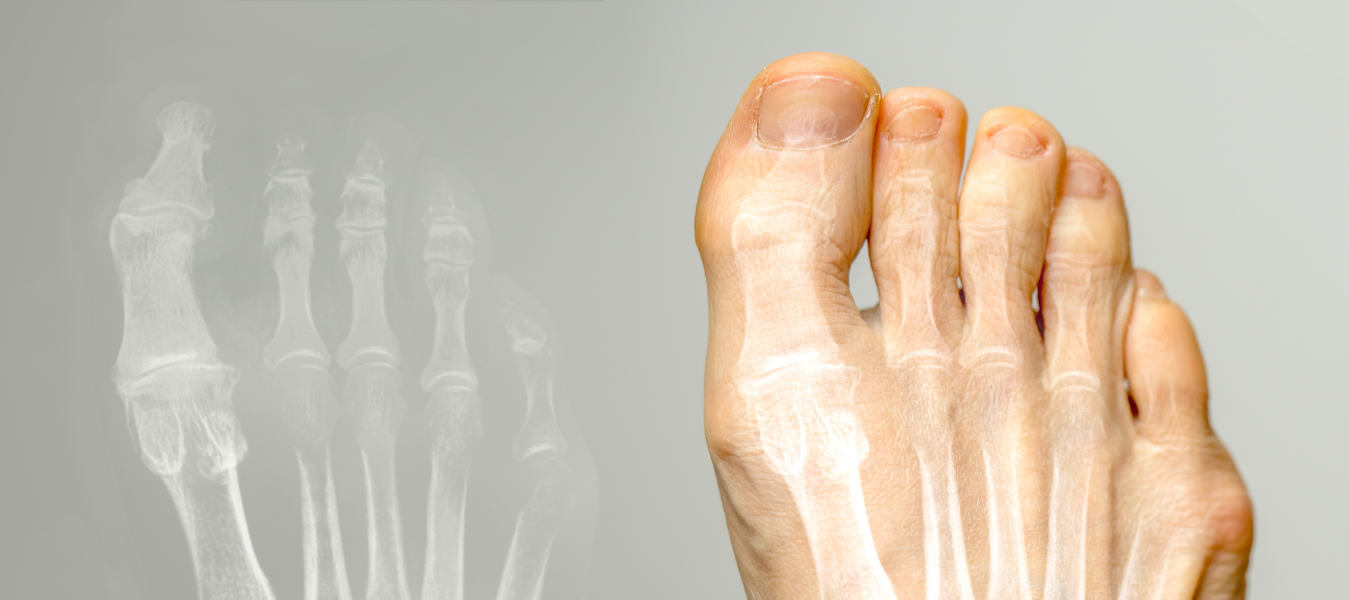

Det tydligaste tecknet på skräddarknuta är att du har fått en knöl på fotens utsida precis vid lilltån. Problemområdet uppvisar en utbuktning som sitter på lilltåns grundled, precis där tån rör vid golvet om du sitter i skräddarställning.

Du kan märka att lilltån pekar inåt mot nästa tå i samband med att knölen uppstår. Det är samma symptom som sned stortå, även kallad Hallux valgus. I vissa fall har knölen en förhårdnad efter att ha skavt mot skons insida en längre tid.

I samråd med sjukvården blir foten skelettröntgad för en bedömning av området. Om skräddarknuta konstateras utförs en dagoperation med lokalbedövning. Läkaren tar bort delar av knölen för att minska bredden på foten och minska obehaget.